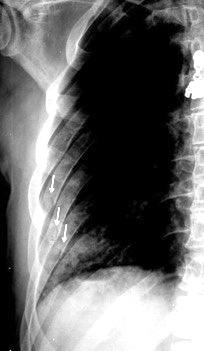

Neumonía a neumococos base izda. con derrame que aumenta.

Broncograma en lateral y en US.

(36-66% en ingresados)